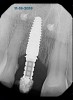

(21.) Postoperative periapical radiograph taken immediately after placement of the implant at site No. 8 demonstrating implant positioning centered with the planned location of the gingival zenith and two titanium alloy tacks that were used to stabilize the resorbable membrane apically.

Figure 21

Prior to the initiation of the surgery, the surgical guide was tried in to confirm proper seating and stability (Figure 15). A flapless approach was not considered because the need for further bone grafting at the time of implant placement had been anticipated through the digital planning. A slightly palatal crestal incision was made, followed by two vertical incisions on the mesial and distal aspects of the edentulous site in order to preserve the papilla and avoid additional esthetic compromise to the anterior sextant. Next, a full-thickness flap was elevated to facilitate removal of the tenting screw and permit visualization of the buccal plate (Figure 16). A standard guided protocol was followed to place the implant, and its final position mirrored that of the digital plan. As predicted, the prosthetically driven implant position resulted in an insufficient buccal plate (Figure 17); therefore, additional guided bone regeneration was performed to reinforce the area and prevent future breakdown (Figure 18 and Figure 19). Making periosteal incisions could have compromised the blood supply to the flap, so instead, it was stretched in order to achieve tension free coronal advancement.31The flap was secured utilizing horizontal mattress sutures with additional supportive interrupted sutures to ensure primary closure (Figure 20). An immediate postoperative periapical radiograph (Figure 21) and CBCT scan (Figure 22) were taken, demonstrating a final implant position centered with the planned location of the gingival zenith.